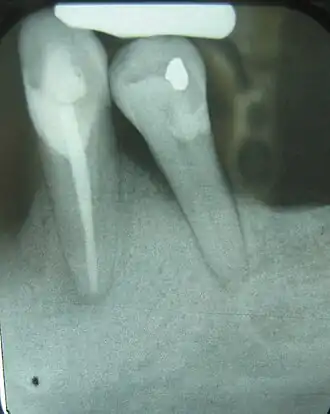

There are many types of investigations in diagnosis of oral and maxillofacial diseases, including screening tests, imaging (radiographs, CBCT, CT, MRI, ultrasound) and histopathology (biopsy).[5]